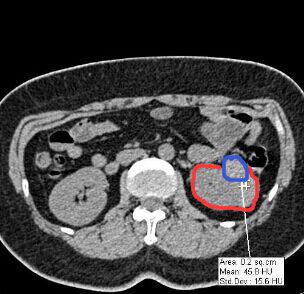

某医院的外科医生需要做一个3D肾脏模型,但CT片拍出的二维图像中,其肿瘤位置只是通过灰色的色阶来表示(临床应用中称之为CT值),如上图中红色圈出来的是肾脏截面,蓝色则为肿瘤位置。从图中可以看出,在CT片子中蓝色部分仅仅比红色部分要白一点。